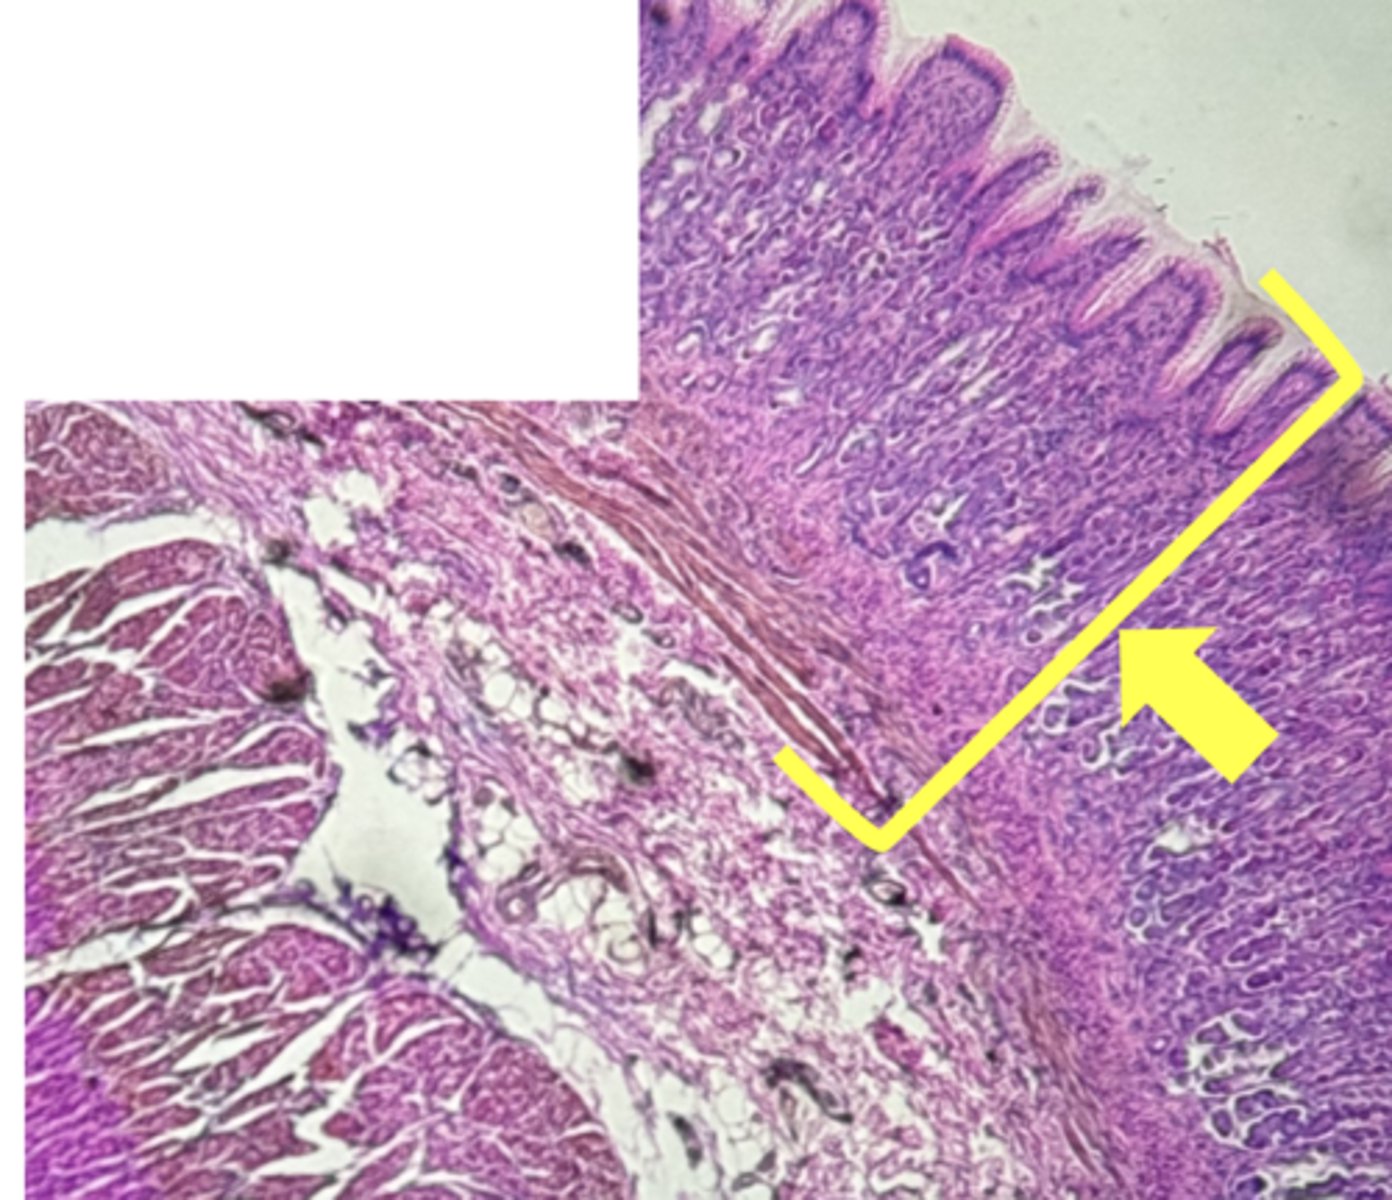

ileum-small intestine

type of tissue

Mucosa

(ilium)

submucosa

muscularis externa

payers patch (KEY CHARACTERISTIC)

circular layer

(ileum)

longitudinal layer

villi

simple columnar epithelium

type of cell

goblet cell- mucous (KEY CHARACTERISTIC)

(ileum-increased # seen here)

type of cell & what it secretes

intestinal crypts

lamina propria

muscularis mucosae